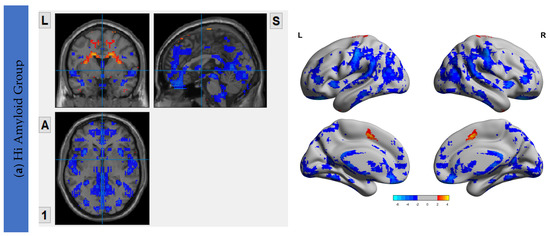

The Aβ protein accumulation was assessed using [18F]flutemetamol uptake maps. The maps for HiAmy and LowAmy groups were displayed in Figure 1. SUVr is a ratio from 0 to 1, with 0 indicating no Aβ protein accumulation and 1 indicating high Aβ protein accumulation.

[18F]flutemetamol PET/CT imaging showing Aβ protein accumulation (SUVr) Maps, showing regions of Aβ accumulations from voxel-wise analysis. (a) shows the regions where Aβ protein distribution in the HiAmy group. (b) shows the regions where Aβ protein distribution in the LowAmy group. The voxel-wise map is adjusted for age and sex. The blue and red colours illustrate the SUVr values according to the scale on the right. When compare Figure 1a,b, the Aβ protein accumulation was much higher in the HiAmy group when compared to the LowAmy group. HiAmy: Patient group with global SUVr > 0.62. LowAmy: Patient group with global SUVr < 0.62.